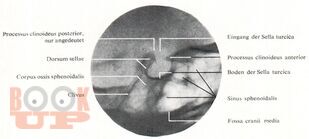

В учебном пособии представлены широкие возможности лучевых методов исследования при патологии области турецкого седла. Большое внимание уделено возможности классической краниографии с учетом новых современных аппаратов, таких как МРТ И КТ.

Методическое учебное пособие иллюстрировано снимками, схемами, дан краткий список литературы. Учебное пособие предназначено для интернов, ординаторов, рентгенологов.